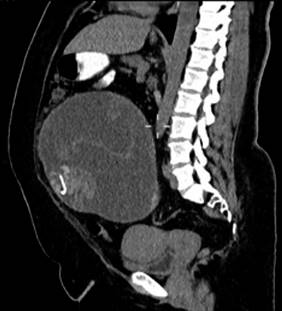

A la exploración física muestra aumento de volumen generalizado en abdomen, indurado, no doloroso a la palpación, peristalsis normoactiva. Estudios de laboratorio dentro de parámetros normales. Rastreo abdominal ecográfico a nivel de hipogastrio con imagen mal definida heterogénea con ecogenicidad de tejidos blandos y áreas lineales hiperecogénicas que proyectan sombra acústica. Tomografía abdominal reporta una imagen ovalada, heterogénea, con pared que realza con el contraste y dos áreas con densidad metal, la cual ejerce efecto de masa sobre estructuras pélvicas (Figura 1). Se realiza laparotomía exploradora identificando masa pseudoquística de 24 × 20 cm y líquido libre escaso, se realiza resección del mismo (Figura 2).